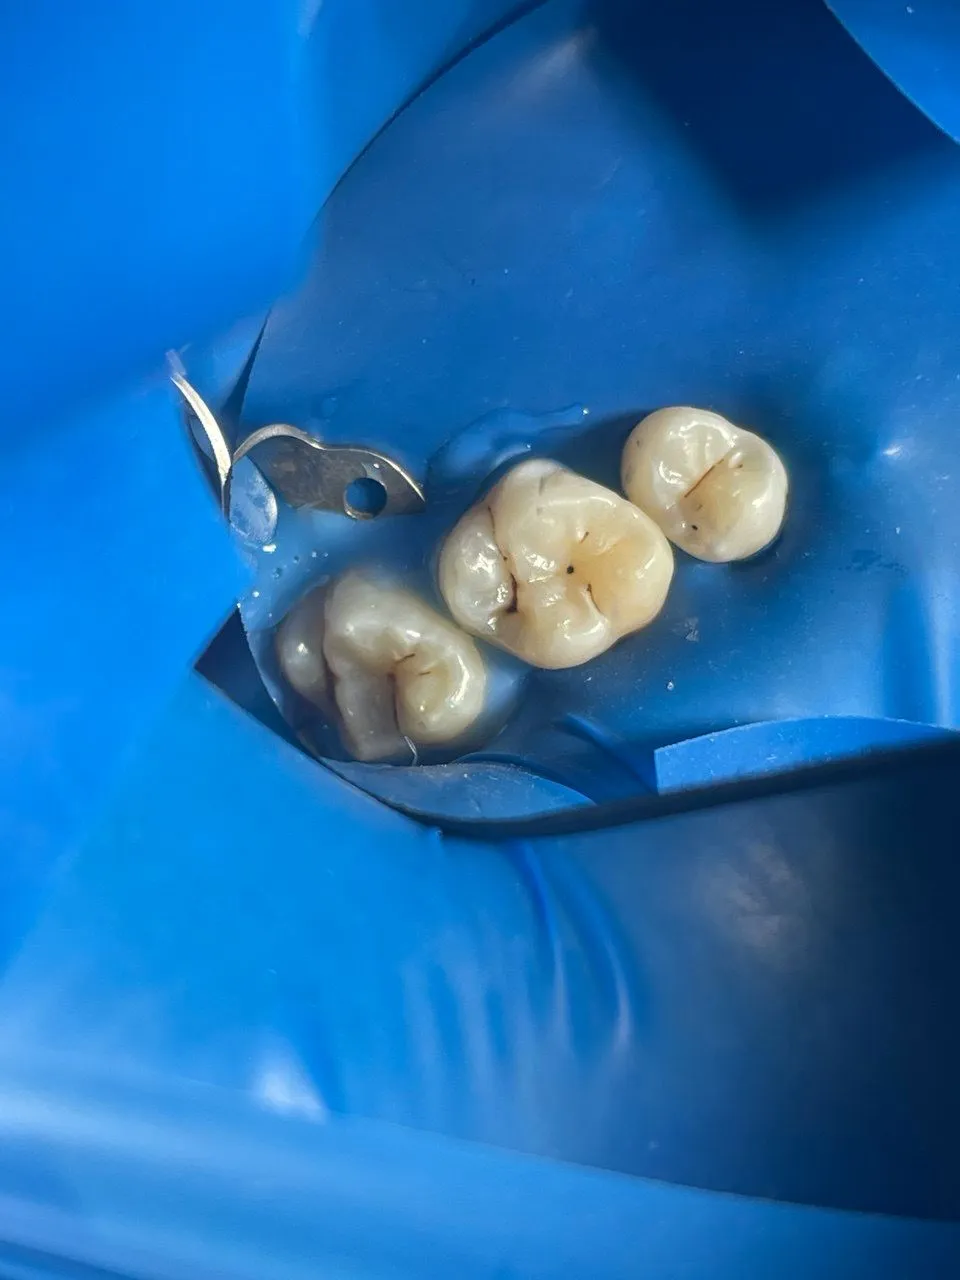

Было пролечено три зуба с диагнозом средний кариес (кариес дентина).